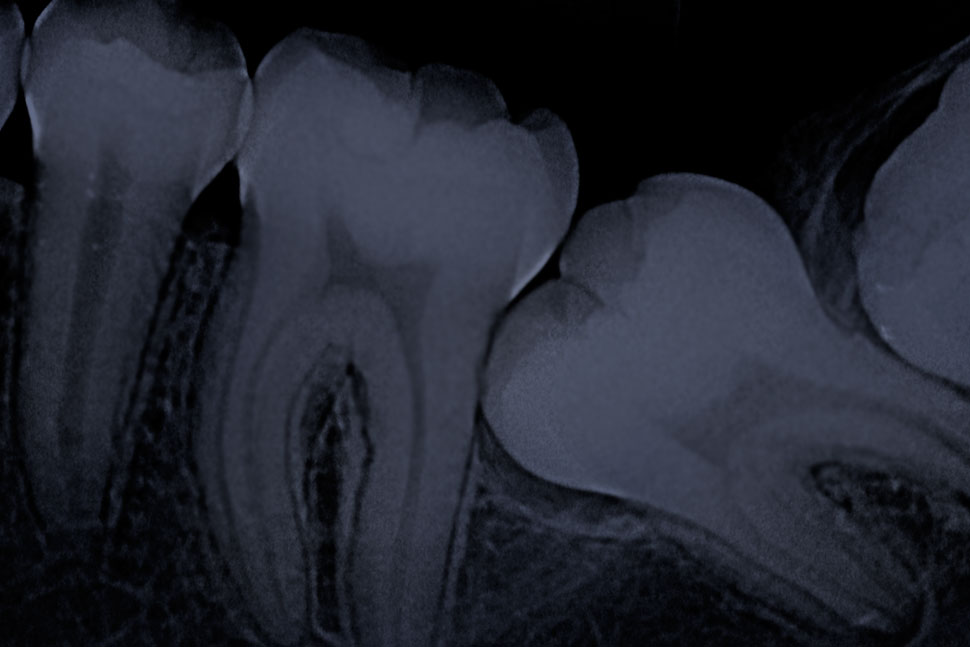

Radiografía Periapical

Enseña uno o dos dientes completos desde la raíz hasta la corona.